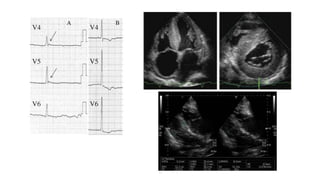

• An electrocardiogram performed on admission showed sinus arrest

and junctional rhythm with a heart rate of 40 beats per minute. Osborn

waves were apparent in leads V4 to V6.

Left ventricular diastolic dysfunction in echocardiography